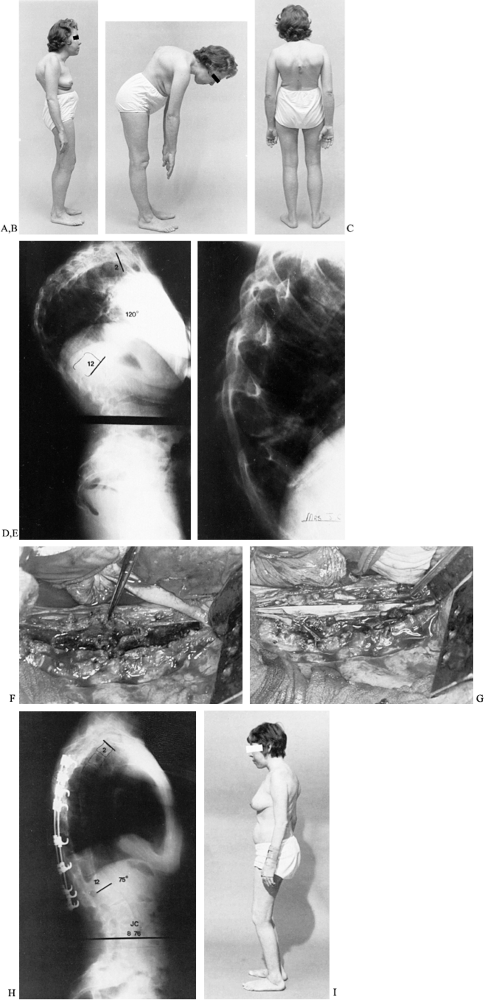

Figure 153.7. A:

A 58-year-old man had severely painful spondylodiscitis at T12–L1, which resulted in an increasing flexion deformity of the thoracolumbar spine. B: A lateral radiograph of T12–L1 shows gross destructive spondylodiscitis at the apex of the deformity. C: A lateral standing 3-foot radiograph shows the weight-bearing line to be anterior to the area of spondylodiscitis, producing shear stress on the lesion. D: A standing lateral 3-foot radiograph after an extension osteotomy of the mid-lumbar spine shows that the weight-bearing line has been shifted posteriorly, converting shear force to compression force at the site of the spondylodiscitis. E: A lateral radiograph at T12–L1, 4 months after surgery, shows spontaneous healing of the area of spondylodiscitis as a result of the conversion of shear stress to compression. F: The patient following healing of the osteotomy and area of spondylodiscitis. The extension osteotomy of his lumbar spine corrected his deformity and allowed spontaneous healing of the spondylodiscitis. |